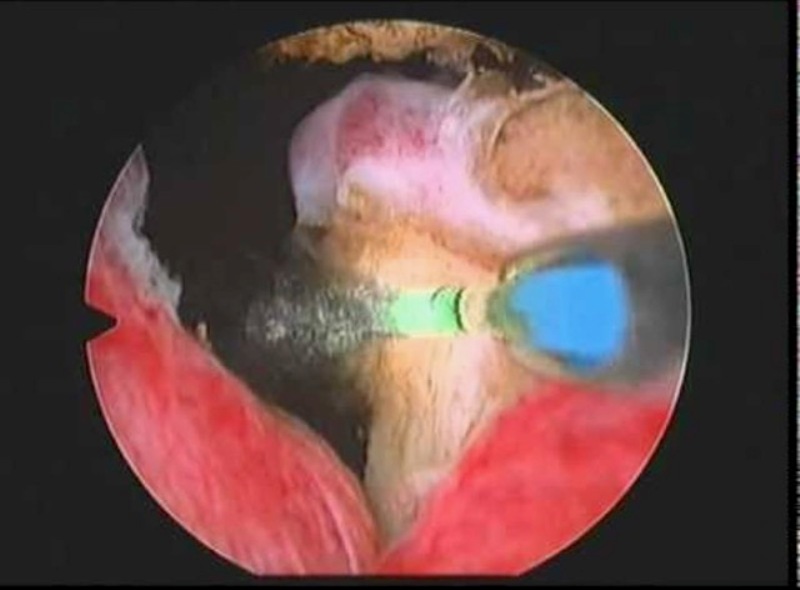

وأشار الدكتور قاسم أن استخدام هذه التقنية الحديثة يعتبر سابقة على مستوى المشافي الفلسطينية وعدد من المشافي الإسرائيلية، مضيفا أن ما يميزها هو أن استئصال غدة البروستات من قشرتها يتم بشكل كامل بواسطة الليزر ودفعها للمثانة ومن ثم تقطيعها لقطع صغير قبيل سحبها، كما أن هذه التقنية تمتاز بكونها آمنة ودقيقة، وتجنب المريض حالة النزيف، كما أن المريض لا يحتاج للمكوث في المستشفى لفترة طويلة، ولا يعاني من الاضطرابات البولية كالحرقة والنزيف وغيرهما.

وأضاف قاسم: "ميزات تقنية ليزر الثولميوم الحديثة تجنب المريض مضاعفات التقنيات القديمة المتمثلة بالشق الجراحي أو المنظار والتي تستخدم بها الكهرباء الحرارية والمحلول المائي (الجلايسين)، حيث يتسبب ذلك أحيانا بنقص شديد في مستوى الصوديوم في الدم، الأمر الذي يشكل خطورة على حياة المريض، كما يصاحبها نزيف حاد وقد تتسبب في حدوث سلس بولي أو حدوث تضيق في مجرى البول".